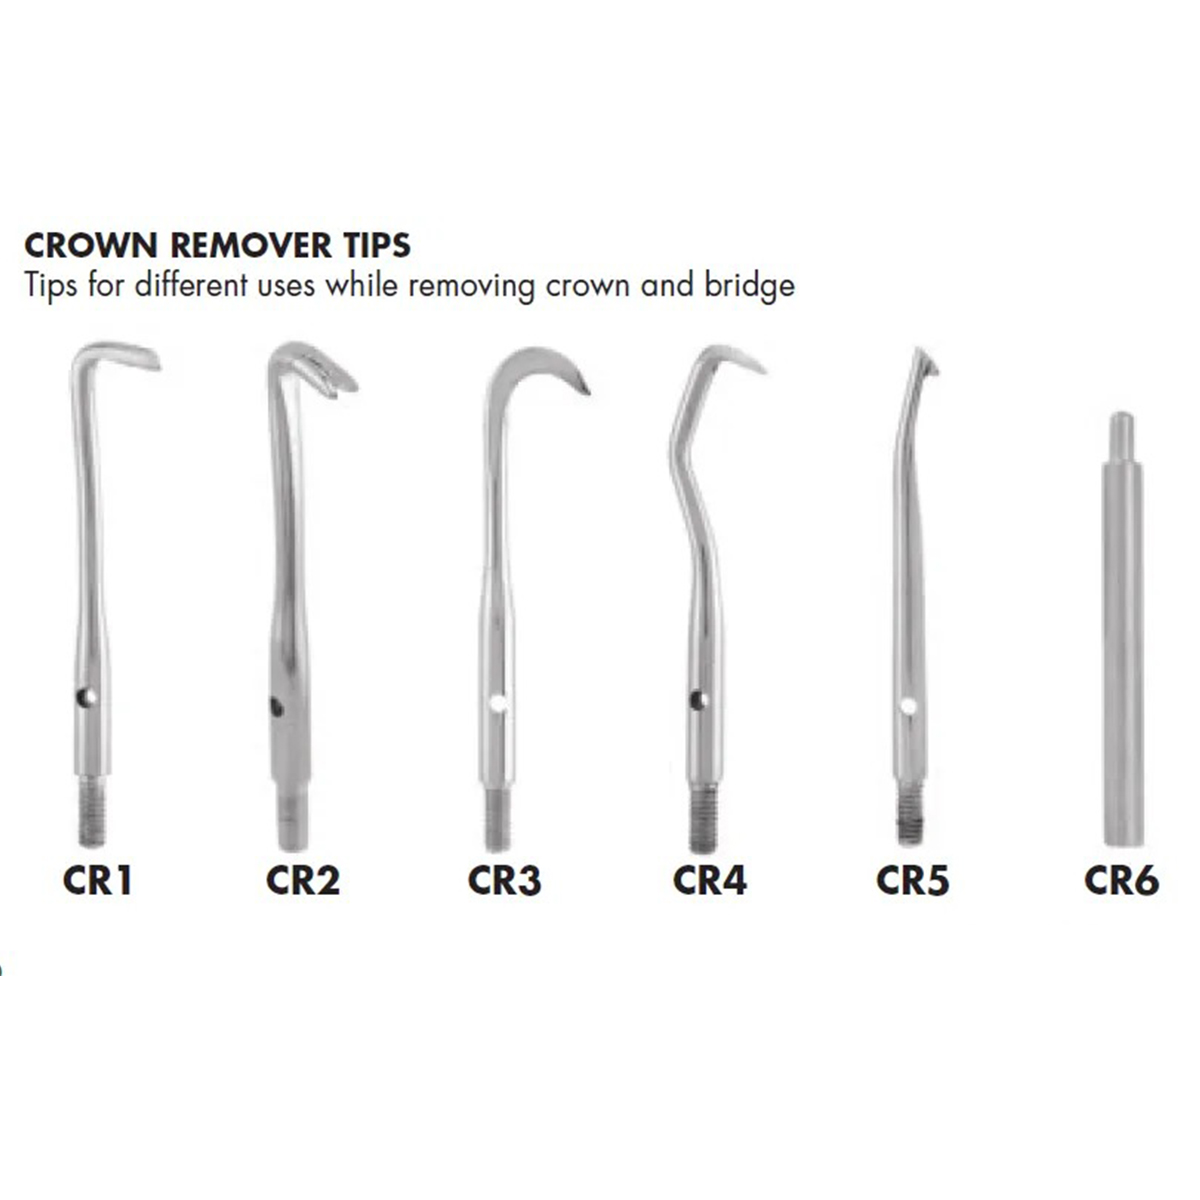

- Automatic Crown Removers: Utilizing mechanical force, automatic crown remover kits ensure precision and ease of use. These kits usually consist of a handheld device that delivers controlled force to dislodge the crown from the tooth structure.

- Manual Crown Removal: Manual techniques involve using crown removing pliers, which provide a strong grip on the crown for gentle extraction. These pliers are designed with specialized tips to grasp the crown securely without causing damage.

- Semi-Automatic Crown Removal: Semi-automatic kits combine manual control with mechanical assistance. These kits include tools that aid in controlled crown detachment, offering a balanced approach to removal.

- Crown Cutting Burs: In cases where the crown cannot be removed intact, crown cutting burs are employed. These burs are designed to cut through the crown material, facilitating its removal in sections.

- Wamkey Kits: Wamkey kits feature unique tools that allow dentists to remove crowns by engaging with the undercuts of the crown, ensuring minimal trauma to the surrounding tooth structure.